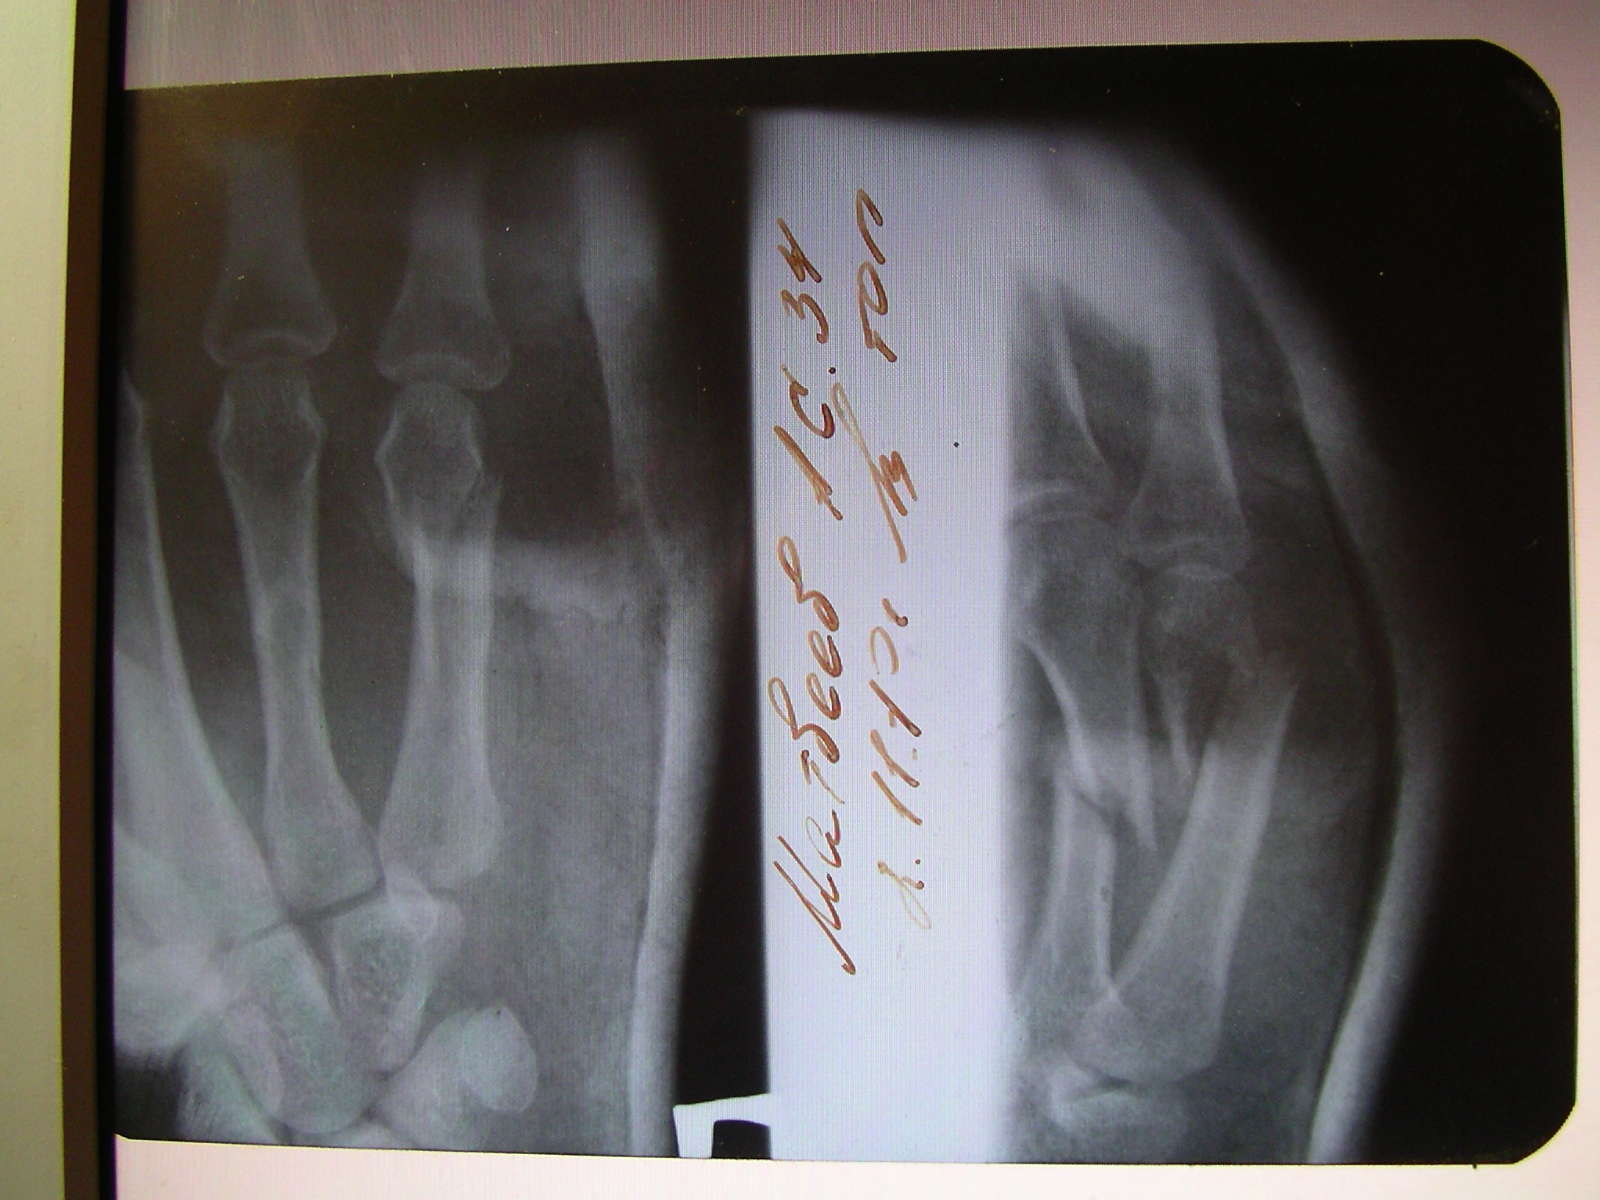

Свекровь(64года)09.05.2012 порвала сухожилие на кисти руки.Она сразу же съездила в травматологическую поликлинику на ул.Краева,сделала снимок,также ей наложили повязку.До 21.06.2012 ходила с повязкой,терапевт во второй городской назначал лечение магнитом(???),но ничего не помогло,после снятия повязки прошел почти месяц,а рука все еще опухшая и положительной динамики нет.По этому поводу свекровь снова обратилась во вторую городскую поликлинику,там назначили мазать индовазином,хондроксидом,суставитом и пчелиным ядом.Всем вышеперечисленным регулярно пользуется,однако никакой положительной динамики нет.Рука опухшая,в кулак не сжимается,с трудом сгибается-разгибается.Где можно получить хорошую консультацию и лечение такой травмы?Заранее спасибо за ответы.